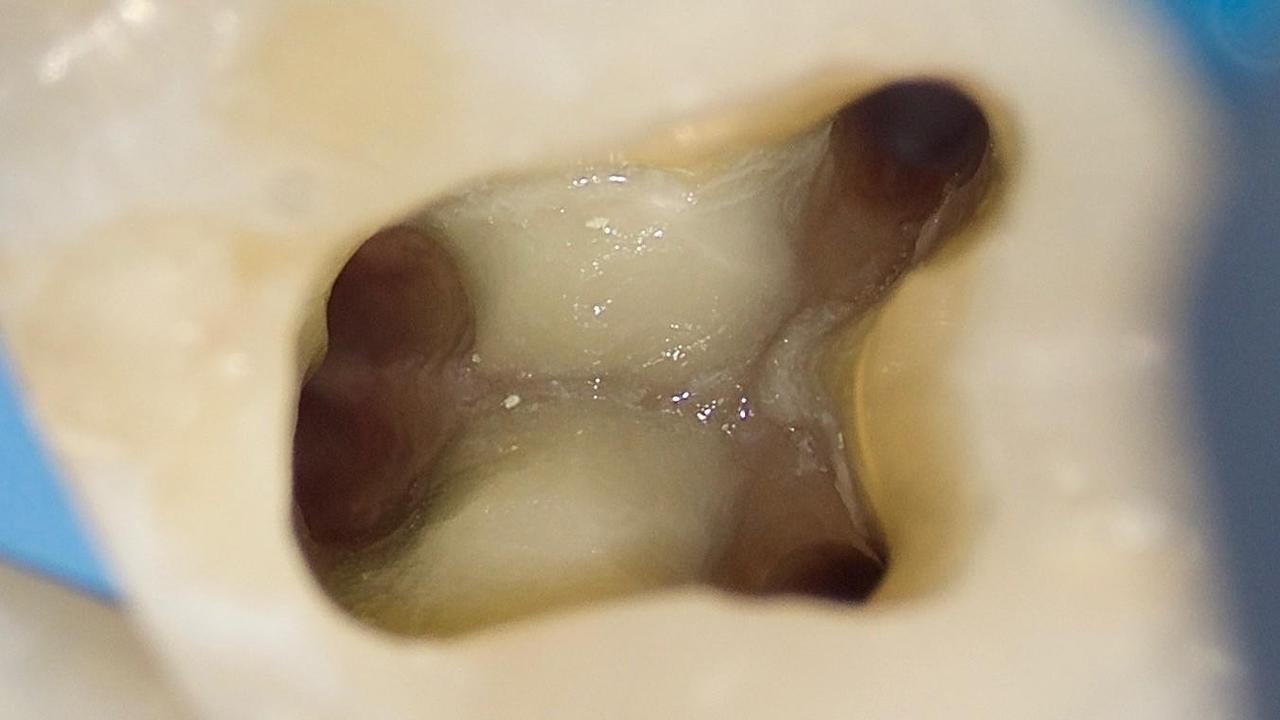

First Mandibular Molar